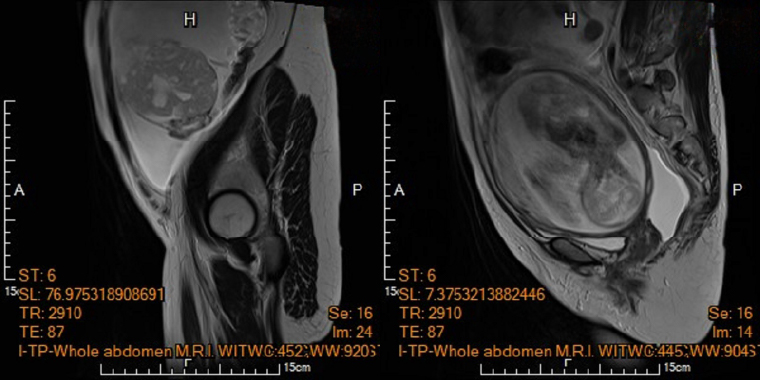

▲圖左為孕婦電腦斷層呈現腹水與卵巢腫瘤,圖右為電腦斷層顯示子宮內胎兒。(圖/馬偕紀念醫院提供)

【NOW健康 楊芷晴/台北報導】懷孕5個月例行性產檢竟意外發現卵巢有惡性腫瘤時,到底要不要終止懷孕?為該名孕婦產檢的馬偕紀念醫院高危險妊娠科資深主治醫師王亮凱表示,李小姐在妊娠20週進行第4次例行性產檢時,腹中胎兒發育情況一切正常,但超音波檢查意外發現孕婦腹腔內積滿大量腹水,及左側下腹部有一個15公分大小、邊界模糊、結構複雜的卵巢腫瘤。

由於孕婦反映有明顯的進食與呼吸困難疑似腸胃道問題,為求謹慎,針對腹水檢體進行細胞檢驗,雖未能於腹水內發現癌細胞,腹部核磁共振影像顯示腫瘤疑似來自左側卵巢,且惡性風險極高,高度懷疑是懷孕中合併卵巢癌。